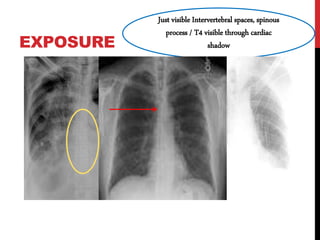

EXPOSURE

Just visible Intervertebral spaces, spinous

process / T4 visible through cardiac

shadow

EXPOSURE Just visible Intervertebralspaces, spinous process / T4 visible through cardiac shadow